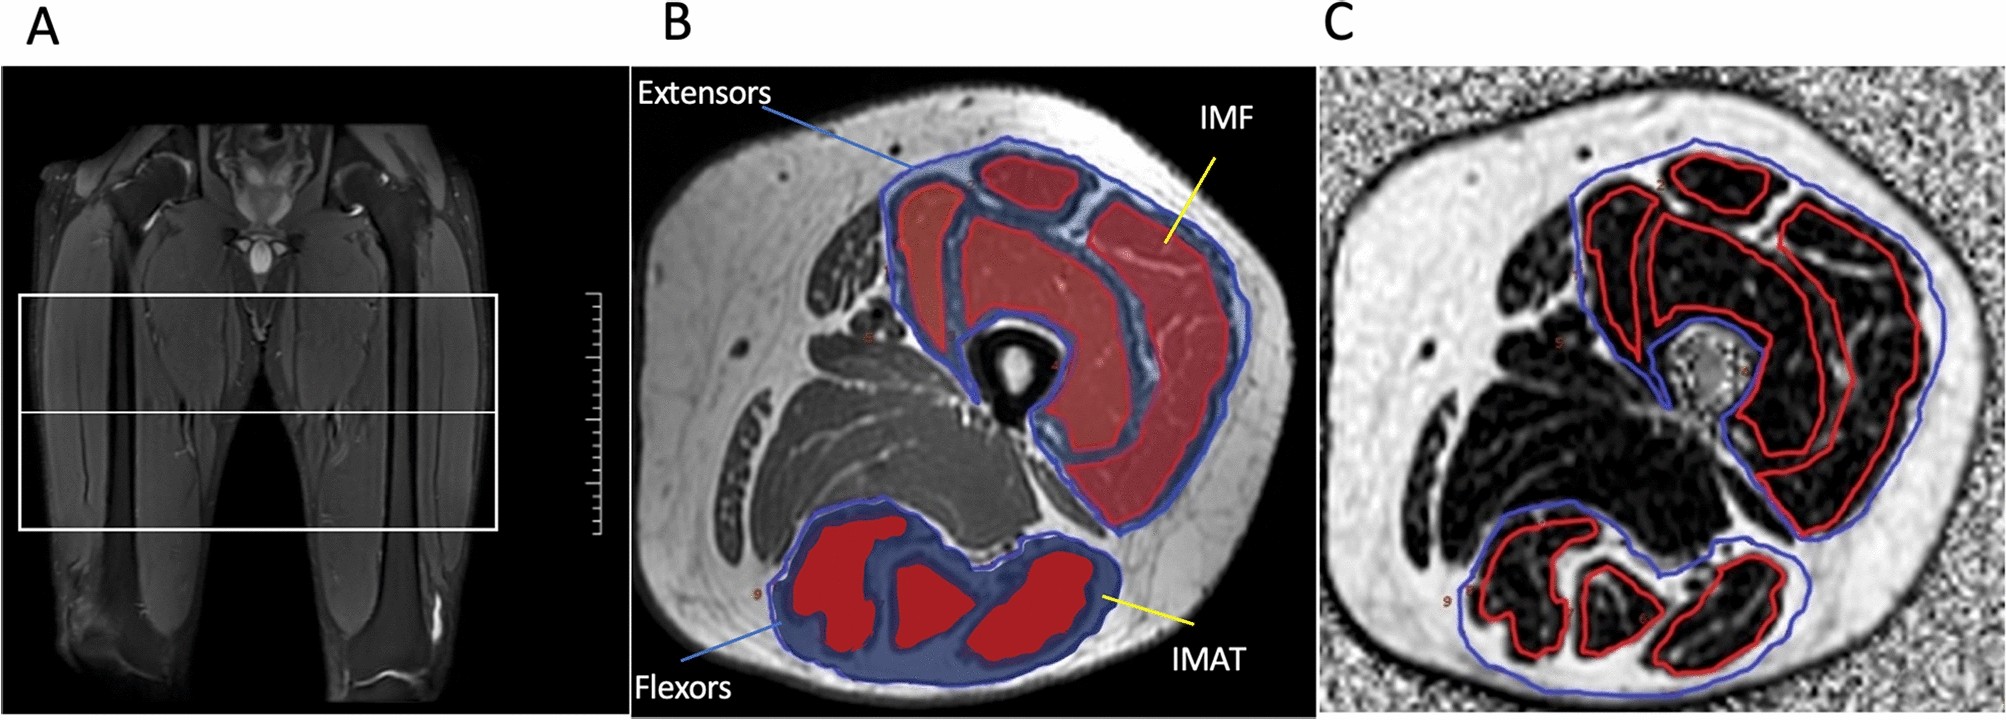

Figure 1

From: Low thigh muscle strength in relation to myosteatosis in patients with type 2 diabetes mellitus

Magnetic resonance image scanning and muscles MRI ROI delineation. (A) MRI scanning range of the thigh (white box). (B) Axial T1WI showing segmentation of thigh muscle and fat. IMF, intramuscular fat; IMAT, intermuscular adipose tissue. (C) PDFF maps of left thigh muscle.